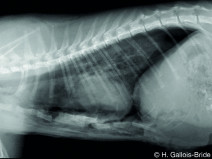

• Alpe d'Huez 2019 : Le thorax à portée de main

Le congrès annuel du GEIM déménage et a choisi, pour son 20e anniversaire, le cadre exceptionnel de l’Hôtel-Spa du Pic Blanc**** à l’Alpe d’Huez ! Pour l’occasion, l’hôtel sera entièrement privatisé. C’est avec un immense plaisir que le GEIM vous y accueillera fin janvier 2019, ainsi que des conférenciers invités du GEC, du GECA et d...

Du 27 janvier au 1 février 2019

L'Alpe d'Huez (38750)

Cardiologie

Chirurgie

Imagerie Médicale

Médecine Interne

G.E.I.M.